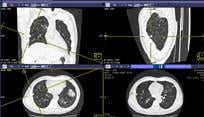

The health system will be able to easily view and analyze medical images and provide diagnostic reports across the enterprise. By implementing McKesson Cardiology, a cardiovascular information system (CVIS), the MLH care team will have complete access to cardiovascular images and reports in real time, including a focus on pediatric cardiology. With Qualitative Intelligence and Communication Systems (QICS), users will be able to collaborate on critical data with the appropriate workflow, while supporting initiatives.

Additionally, MLH will leverage McKesson Study Share a web-based knowledge management system, and McKesson Enterprise Image Repository to help simplify enterprise-wide access to imaging information. Physicians will now have the ability to chat, launch a context-sensitive case for review, agree or disagree on the assessment and immediately go back to their normal workflow from any computer. This will help improve image management and staff collaboration. By reducing the complexity of interfaces across the enterprise, MLH will not only be able to improve decision support, but will also be able to lower the costs associated with interfaces and help decrease the need for future migrations.